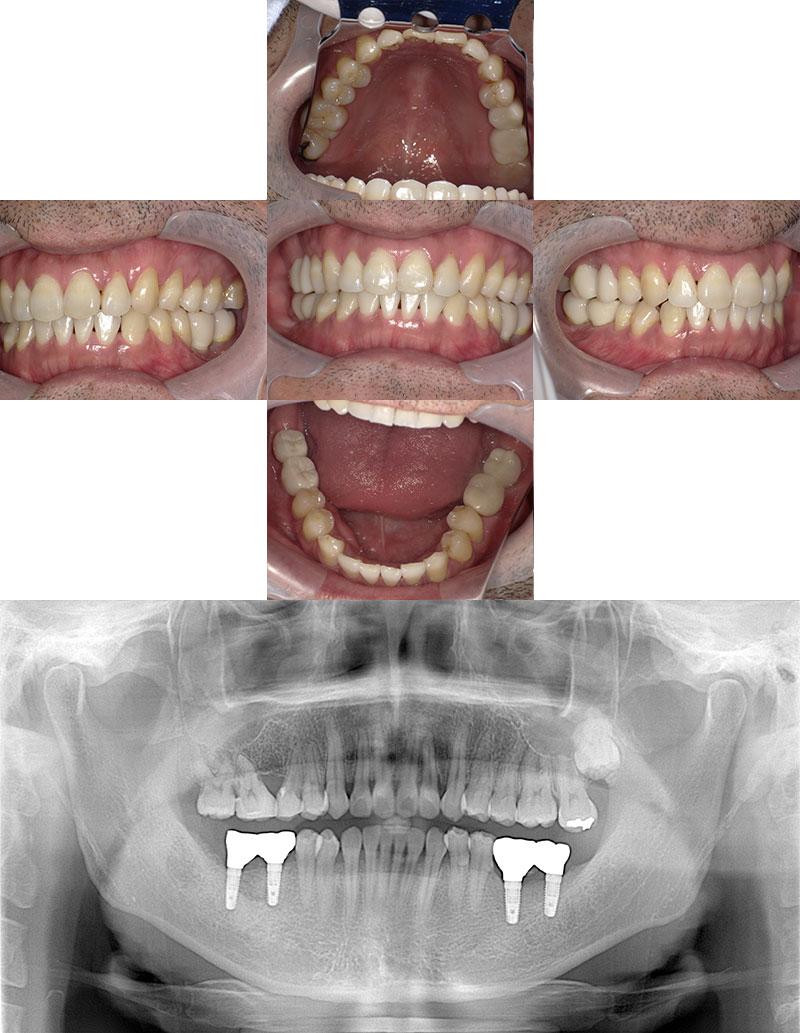

インプラント症例

治療前

Before

治療後

After

年齢 40

性別 女性

主訴 右下の歯茎が腫れを繰り返す